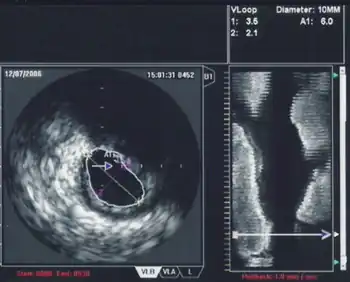

3D TEE is a technology developed to improve upon the limitations of 2D tomography. With the introduction of the matrix TEE probe, 3D TEE can collect real-time 3D images that provide a comprehensive view of the heart structures, leading to better understanding and decision making during cardiac procedures. The technique acquires a volumetric data set and displays it in custom orientations, allowing for greater depth and understanding of heart structures compared to 2D echocardiography.[7]